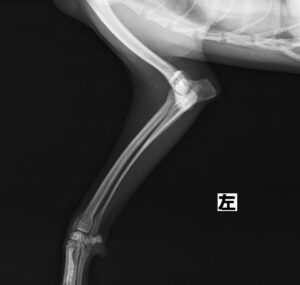

階段からころげおちてかかりつけ医を受診し、X線にて左側「上腕骨外顆骨折」を認めたため、当院の整形外科にご紹介いただきました。この症例は、尺骨の骨切り術を併用し外顆の骨折部分を整復しています。術後の経過は良好で、手術から7ヶ月後に尺骨のインプラントを除去し、治療終了としました。